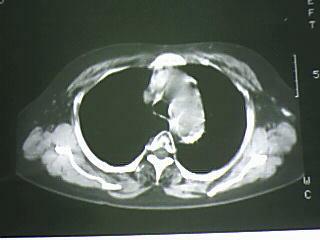

以下是引用bmw011在2009-4-14 19:14:00的发言:[br]右肺继发型肺结核---纵隔淋巴结多发钙化----左肺支扩。支持

以下是引用杀毒软件在2009-4-14 17:52:00的发言:[br]考虑---右肺继发型肺结核---纵隔淋巴结多发钙化----左肺支扩

以下是引用黑白光影在2009-4-14 20:36:00的发言:[br]右肺继发型肺结核;左下慢性支气管炎性病变。